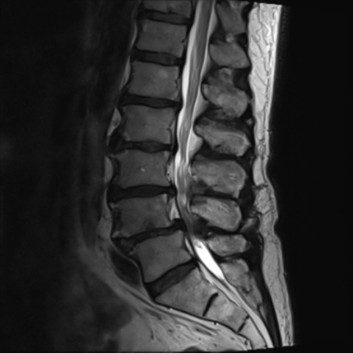

급성 디스크 손상 및 디스크 탈출증

허리 디스크에 의한 급성 통증 발생 시에도 심부신경 주사치료를 통해 효과적으로 통증을 조절 할 수 있습니다. 갑작스런 자극에 의한 신경의 통각 과민을 예방하고 붓고 파열 된 디스크의 크기를 줄임으로써 수술 없이 안전하게 치료가 가능합니다. 효과적인 치료를 위해 반복해서 치료 해야 합니다. 심각한 디스크의 파열은 수술이 필요 할 수도 있습니다.

척추관 협착증의 치료

좁아진 척추관에 의해 발생한 협착증은 심한 경우 주사로 좁아진 공간을 넓게 할 수 없습니다. 다만 심부신경주사치료를 통해 척추관을 효과적으로 감압 할 수 있으며 신경에 대한 주변 조직의 압박을 줄이고 자극과 유착을 제거 합니다. 주사로 해결 되지 않는 경우 신경성형술 등의 시술을 고려 할 수 있으며 운동신경손상 및 통증 정도에 따라 수술을 시행 해야 하기도 합니다.